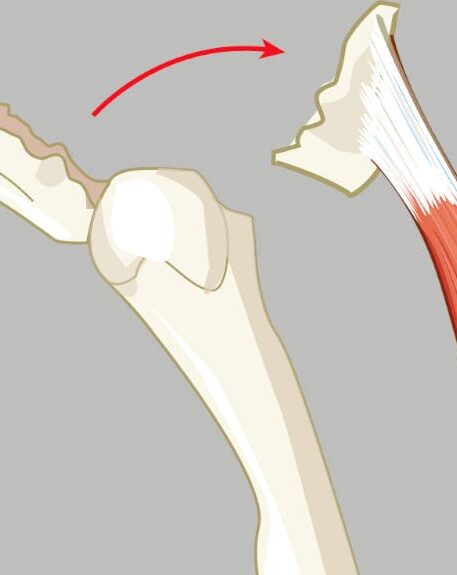

Avoluzijski

ZLOM

Najpogosteje se pojavi:

- pri otrocih in mladih športnikih,

- pri hitrih spremembah smeri, udarcu žoge ali eksplozivnih gibih,

- pri ramenih, kolenih, stopalih in kolkih.

01. Kako pride do avoluzijskega zloma?

Poškodba nastane nenadoma, ob silovitem in eksplozivnem krčenju mišice, na primer pri:

- udarcu žoge,

- hitri spremembi smeri teka,

- poskoku ali doskoku,

- sprintu ali startu iz mirovanja.

Otroci in mladostniki pogosto povedo, da so ob poškodbi začutili nenadno pekočo ali ostro bolečino, zaradi katere niso mogli nadaljevati športne aktivnosti.

03. Simptomi avoluzijske frakture

- nenadna močna bolečina ob poškodbi,

- pekoč občutek v prizadetem predelu,

- oteklina in lokalna občutljivost,

- bolečina ob aktivaciji mišice,

- omejena gibljivost,

- nezmožnost nadaljevanja športne aktivnosti.